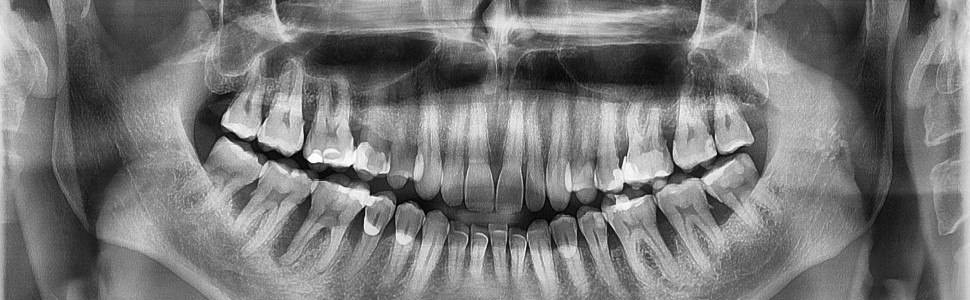

Przedstawiony artykuł stanowi szczegółową analizę elementów wywiadu lekarskiego i badań klinicznych niezbędnych do ustalenia rozpoznania i planowania leczenia pacjentów z problemami w przyzębiu. Autorzy w precyzyjny sposób podkreślają znaczenie zarówno komunikacji z pacjentem, jak i obiektywnych pomiarów parametrów klinicznych. Kompleksowe podejście do badania przyzębia z uwzględnieniem żmudnego sondowania kieszonek przyzębnych oraz właściwego zapisu uzyskanych danych wskazuje na profesjonalizm i znaczenie diagnostyki w planowaniu terapii oraz w monitorowaniu jej wyników.

Kluczowym elementem tekstu jest podkreślenie roli wywiadu lekarskiego jako pierwszego etapu diagnostyki. Autorzy zwracają uwagę na konieczność zadawania pytań otwartych, które pozwalają lepiej zrozumieć dolegliwości i oczekiwania pacjenta. Pytania dotyczące krwawienia dziąseł, ruchomości zębów czy nawyków higienicznych oraz zwrócenie uwagi na palenie tytoniu, świadczą o całościowym podejściu do problemu. Jest to niezwykle istotne, ponieważ pozwala klinicyście postawić trafne rozpoznanie, ale także uświadomić pacjentowi znaczenie jego współpracy i zaangażowania w proces leczenia.